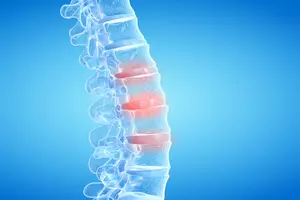

일상생활에서도 지장을 줄 정도로 심한 통증이 발생하는 경우 척추측만증의 중증 증상일 수 있습니다. 통증은 척추 변형으로 인한 신경 압박, 염증, 근육 경련 등에 의해 발생합니다. 앉거나 서있을 때, 운동 후, 심지어 밤에도 통증이 지속될 수 있습니다.

척추 측만증으로 인해 척추에 부담이 가중되어 허리 통증이 발생할 수 있습니다. 특히 운동 후, 오랜 시간 서있거나 앉아 있을 때 통증이 심해질 수 있습니다. 초기에는 경미한 통증이지만, 측만증이 진행될수록 만성적인 통증으로 악화될 수 있습니다.